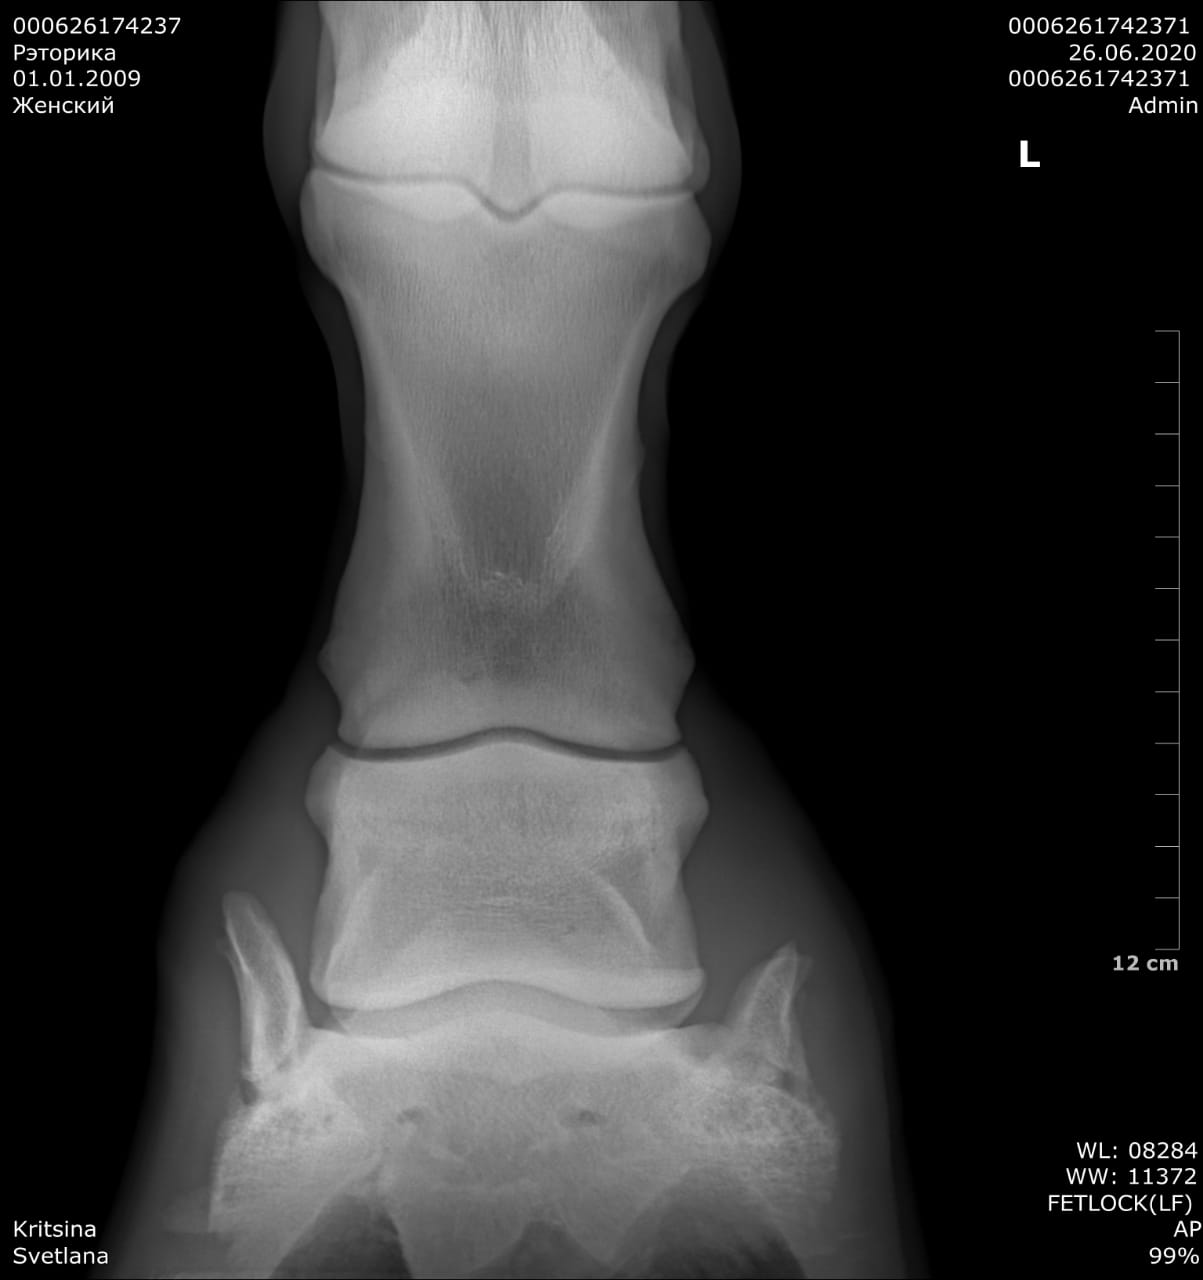

Результаты рентгенологического исследования:

Правая грудная конечность – оссификация латерального хряща копытной кости.

Левая грудная конечность – оссификация латерального хряща копытной кости.